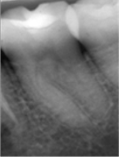

En 2011 concurre paciente de sexo masculino, de 22 años, por caries profunda en pieza 38. Radiográficamente se destaca la cercanía de la cavidad cariosa con respecto a la amplia cámara pulpar (Fig. 3a). Se diagnostica CPPA, luego de eliminar la dentina necrótica reblandecida superficial con cucharita de dentina y verificar su vitalidad con test de fresado. En la evaluación dentinaria se constata dentina de color marrón, blanda y húmeda. Se planifica Técnica de eliminación de caries en etapas. La Fig.3b muestra eliminación total de caries de paredes laterales con control colorimétrico sin tocar la pared pulpar.